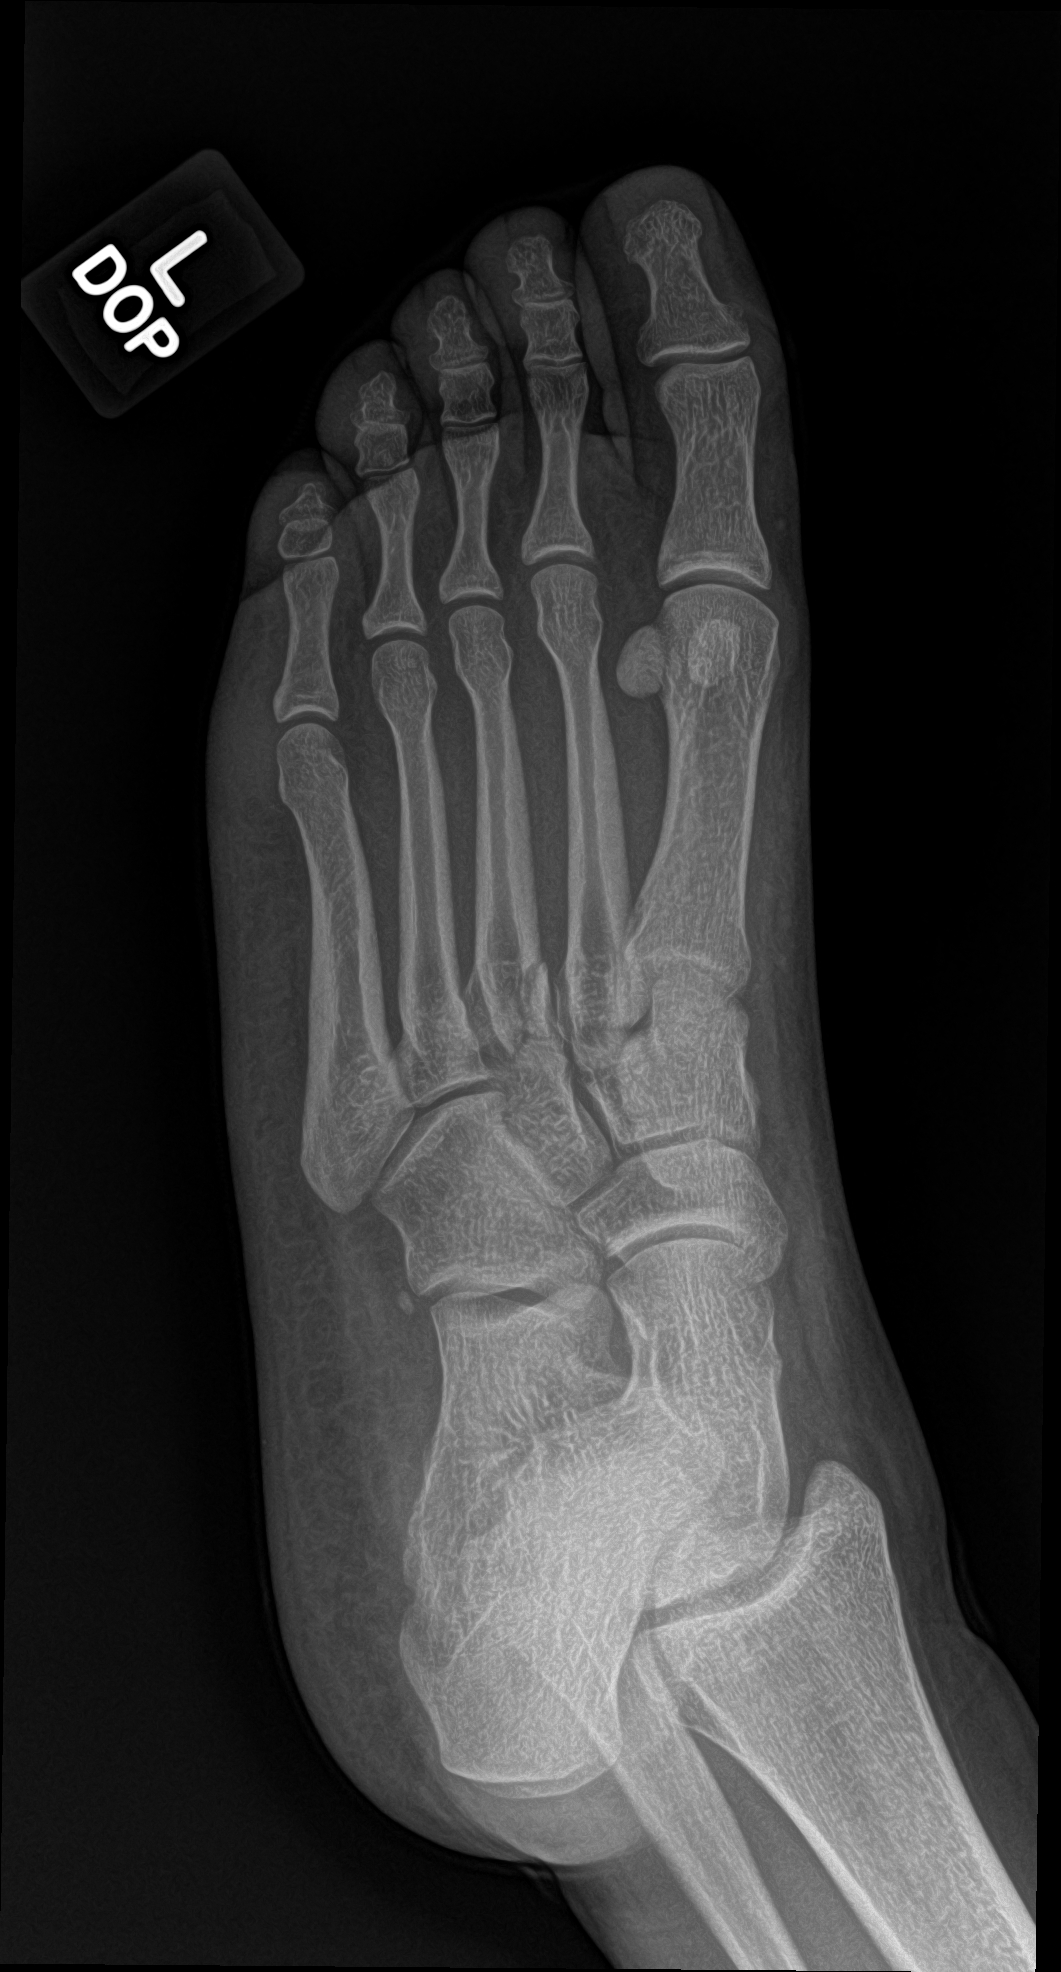

A 21 year old female with left forefoot pain after rolling her foot 2 weeks ago.

base of the 3rd metatarsal fracture